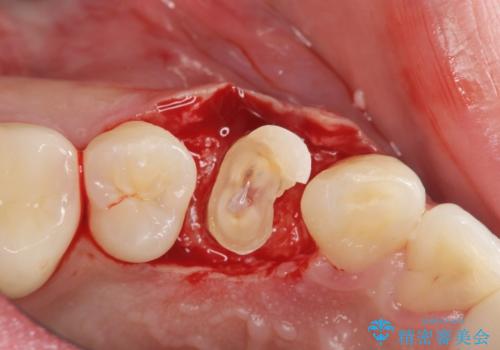

検査の結果、虫歯が大きくなりすぎたせいで薄くなった歯が欠けてしまった経緯が考えられました。

レントゲン画像上で歯茎の深いところまで虫歯になっており、保険治療では抜歯適応になってしまいます。

今回は虫歯の深いところが歯茎のラインにくるまで部分矯正で引っ張り出し、適合の良いかぶせ物を装着しました。

初診時の状態では虫歯が大きすぎて取り切ることができなかったため、まず歯を骨から引きあげて虫歯がしっかり除去できる状態にしました。